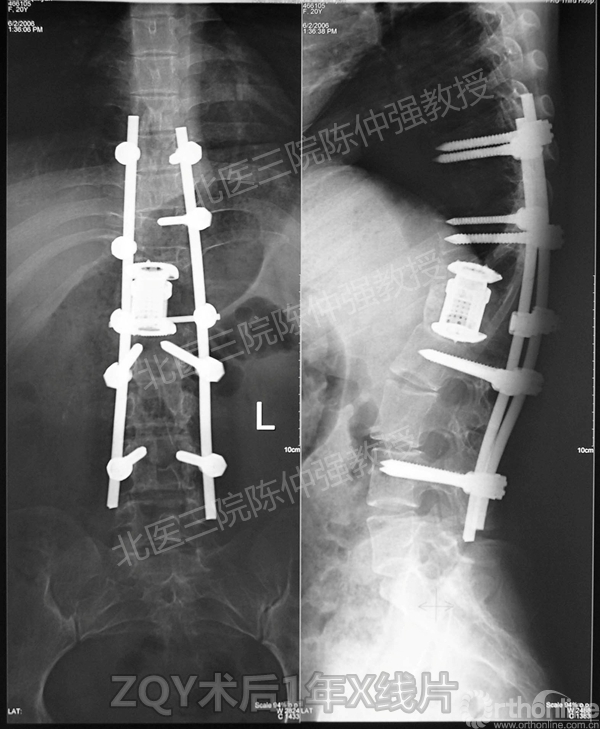

ZQY术后1年

患者女性17岁,胸腰椎陈旧结核性侧后凸畸形,局部呈“麻花状”扭转,无神经功能受损表现。2005年,陈仲强教授带领团队实施后路+侧前方联合入路脊柱节段切除、双轴旋转矫形术。术后患者外观显著改善,神经功能正常。术后随访证实患者截骨矫形节段骨性融合良好,矫形效果持续良好。